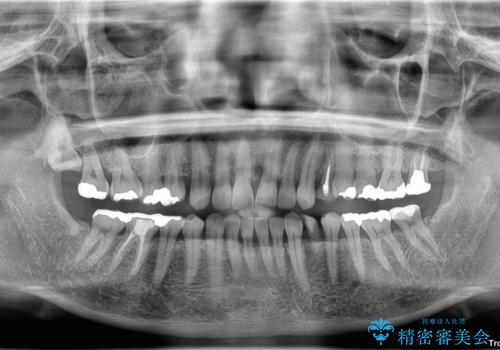

診査の結果、左下に残存していた乳犬歯が水平的に破折しており、残念ながら保存は困難な状態でした。

また、右下にはスペースがあり、左上にも乳犬歯が残存しているという状態で、治療方法としては矯正治療を含めた複数の選択肢が考えられました。